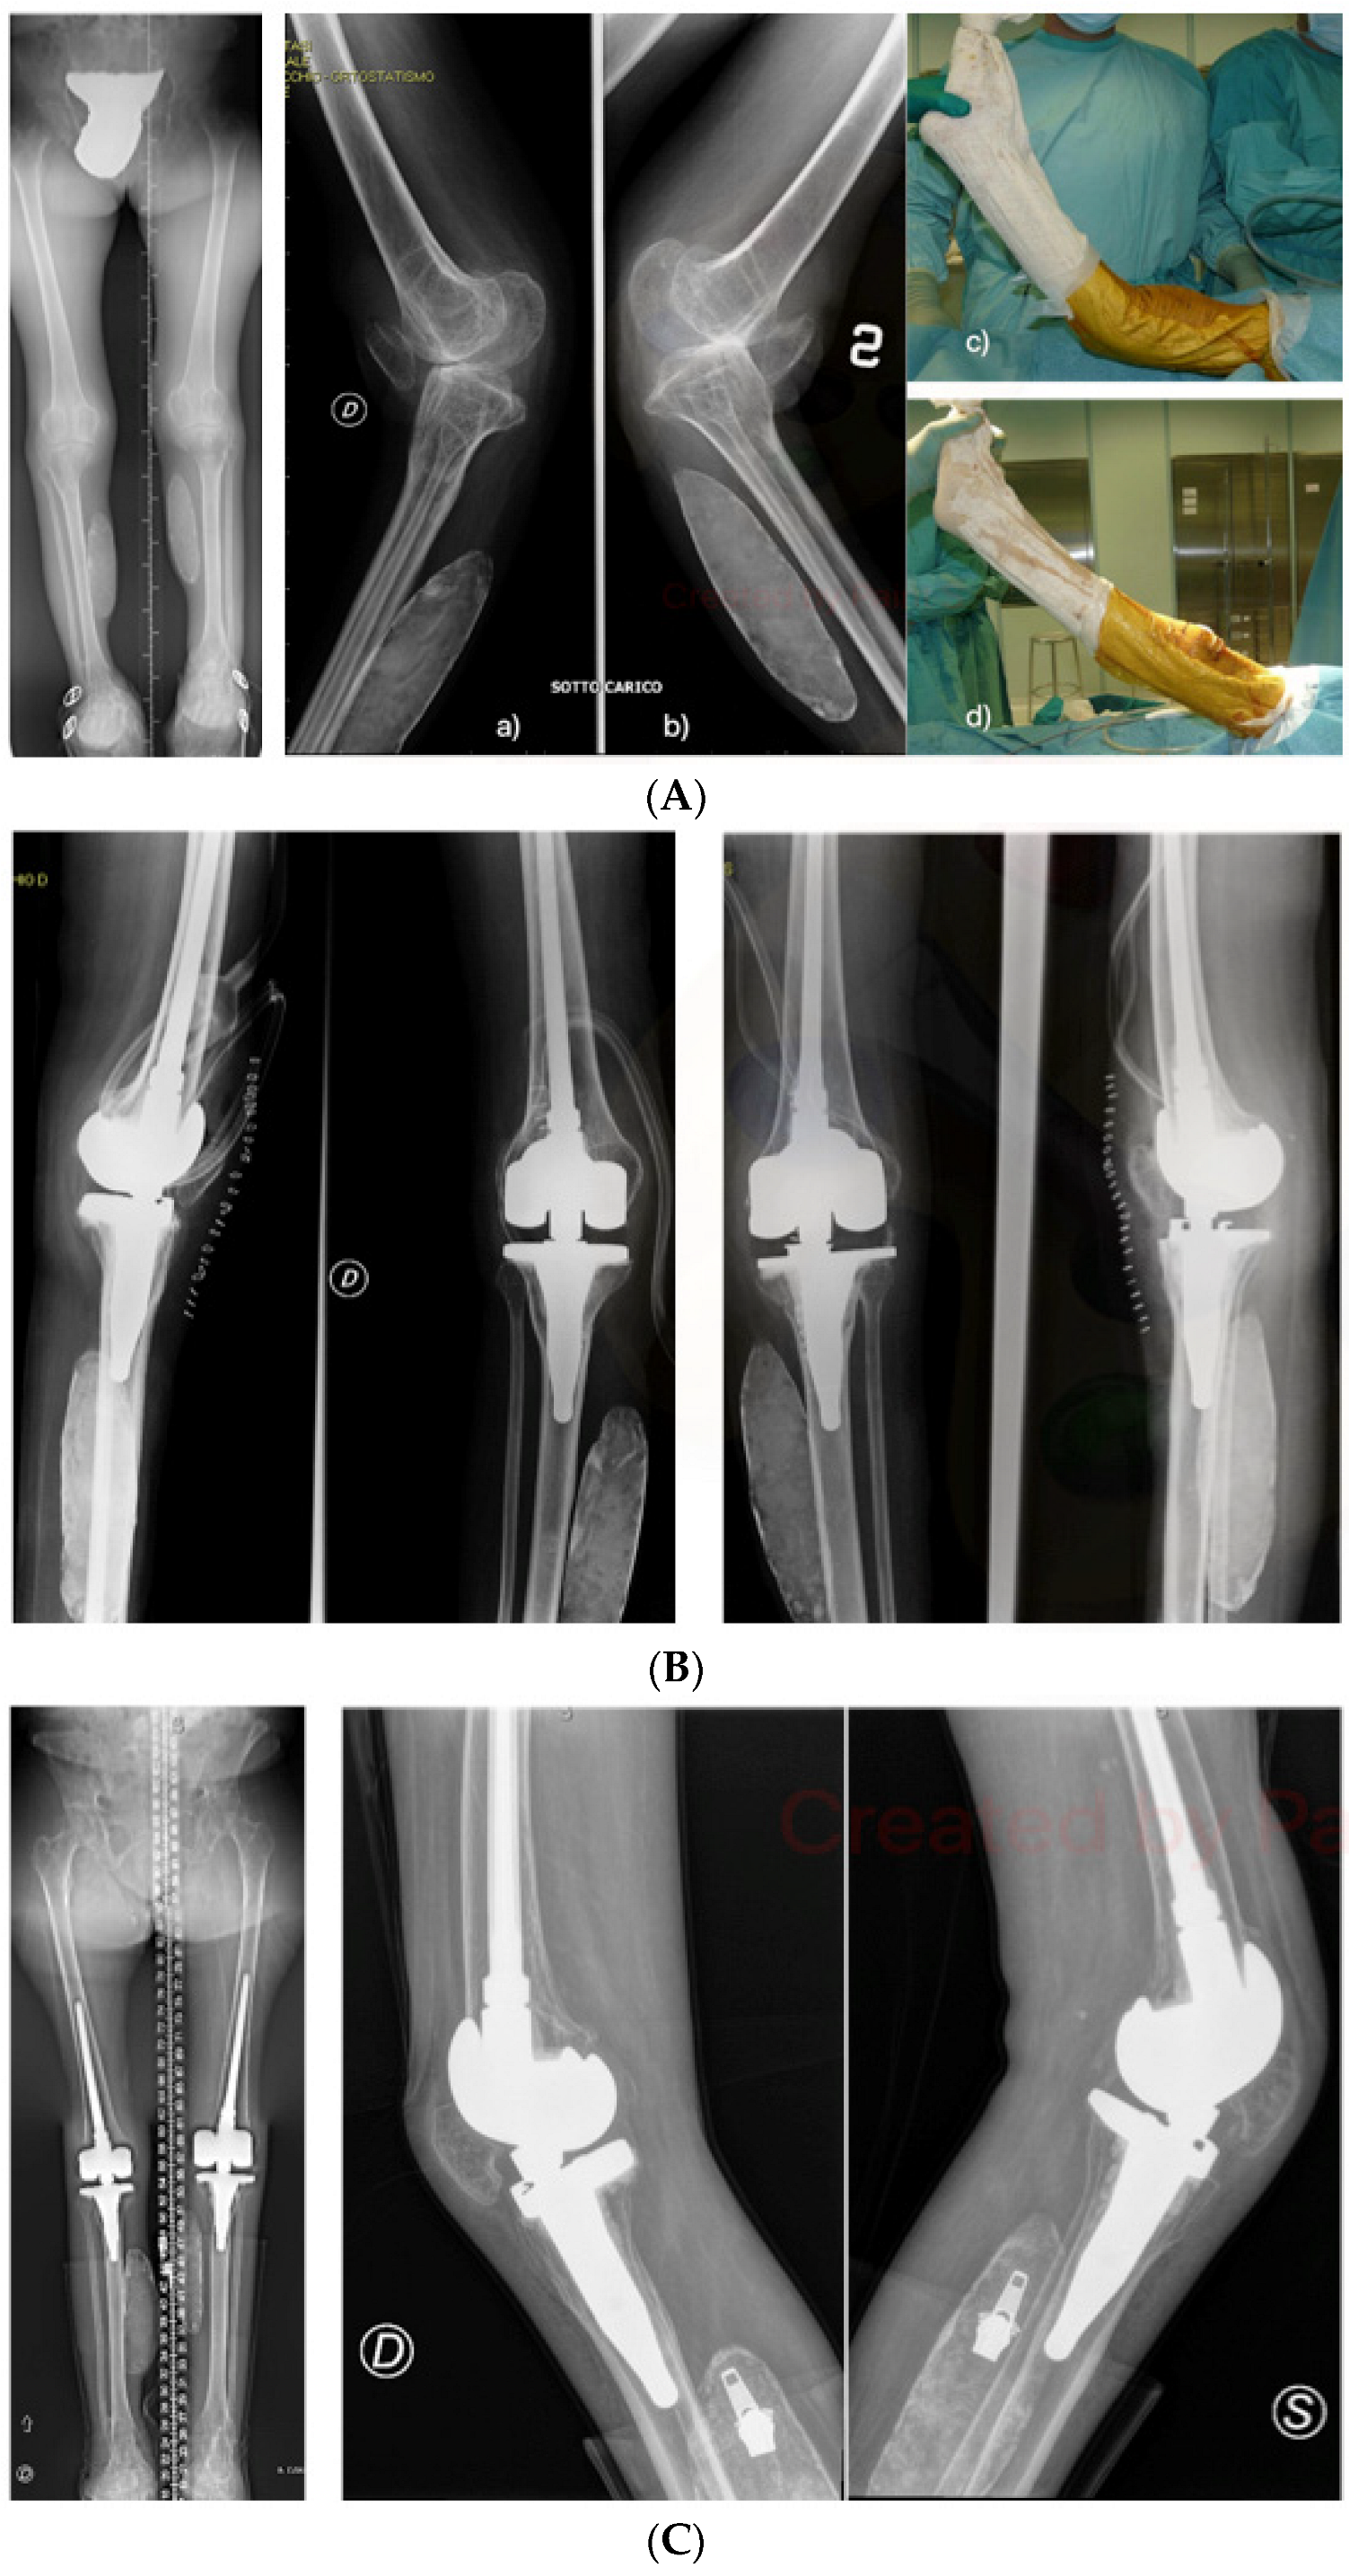

In the series reported in the present study, hyperextension was the most frequently encountered deformity in the preoperative phase: recurvatum was present in 9 cases out of 12 and in some patients it was found to be of an extreme degree (Table 1; Figure 3). In all cases, in order to preserve the functional compensation mechanism, a minimal postoperative residual knee hyperextension was guaranteed (about 3°, built-in in the Zimmer NexGenTM implant design).

Figure 3.

(A) Weight-bearing X-rays in bilateral gonarthrosis with severe hyperextension instability (a,b) following poliomyelitis. Intraoperative images of left knee recurvatum before (c) and after surgery (d). (B) Postoperative weight-bearing radiographic control after bilateral RHK prosthesis implantation, with slight residual hyperextension of the knee. (C) Radiographic control at 12 years.